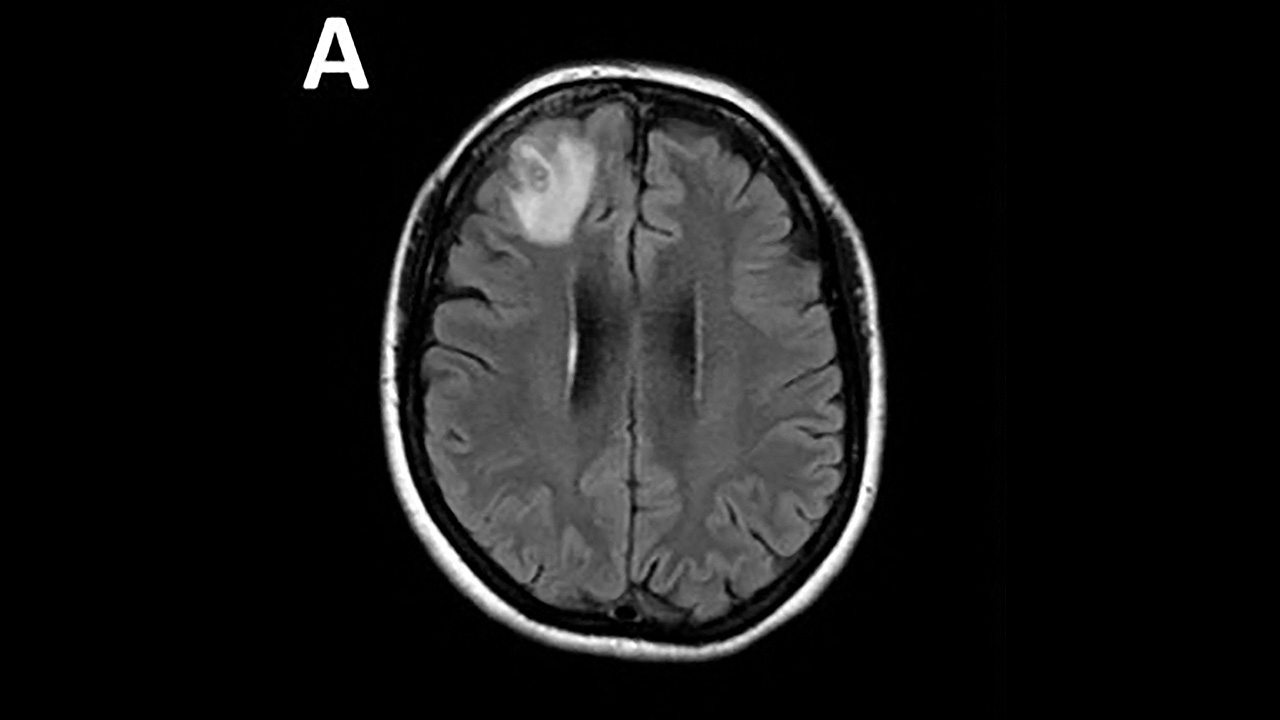

เมื่อวันที่ 29 ส.ค. 2566 สำนักข่าวต่างประเทศรายงาน โรงพยาบาลแคนเบอร์ราในเมืองแคนเบอร์รา ประเทศออสเตรเลีย ได้ตรวจพบความผิดปกติในสมองของหญิงรายหนึ่งวัย 64 ปี และเมื่อแพทย์ได้ตรวจอย่างละเอียดพบว่า ความผิดปกติดังกล่าวคือการที่มีพยาธิตัวกลม (Ophidascaris Robertsi) ยาวประมาณ 8 เซนติเมตร ยังมีชีวิตอยู่ในสมองผู้หญิงคนนั้น ทำให้เธอกลายเป็นผู้ป่วยแรกของโลกที่มีพยาธิชนิดนี้อยู่ในร่างกาย

‘Ophidascaris Robertsi’ เป็นพยาธิตัวกลม ที่พบได้ปกติในงู ซึ่งผู้ป่วยหญิงดังกล่าวก็อาศัยอยู่ใกล้ทะเลสาบซึ่งเป็นแหล่งที่อยู่อาศัยของงูหลาม จึงทำให้ คณะแพทย์สันนิษฐานว่า ถึงแม้หญิงวัย 64 ปีจะไม่ได้สัมผัสงูโดยตรง แต่เธอชอบเก็บพืชพันธุ์บริเวณรอบ ๆ ทะเลสาบไปปรุงอาหาร และพืชเหล่านั้นมีอุจจาระที่มีปรสิตของงูปนเปื้อนอยู่